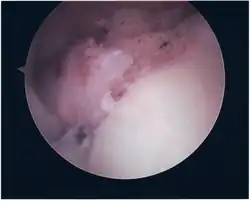

Surgical treatment of SLAP tears has become more common in recent years. The success rate for repairing isolated SLAP tears is reported between 74-94%.[10] While surgery can be performed as a traditional open procedure, an arthroscopic technique[11] is currently favored being less intrusive with low chance of iatrogenic infection.[12]

Procedure

Following inspection and determination of the extent of injury, the basic labrum repair is as follows.

- The glenoid and labrum are roughened to increase contact surface area and promote re-growth.

- Locations for the bone anchors are selected based on number and severity of tear. A severe tear involving both SLAP and Bankart lesions may require seven anchors. Simple tears may only require one.

- The glenoid is drilled for the anchor implantation.

- Anchors are inserted in the glenoid.

- The suture component of the implant is tied through the labrum and knotted such that the labrum is in tight contact with the glenoid surface.